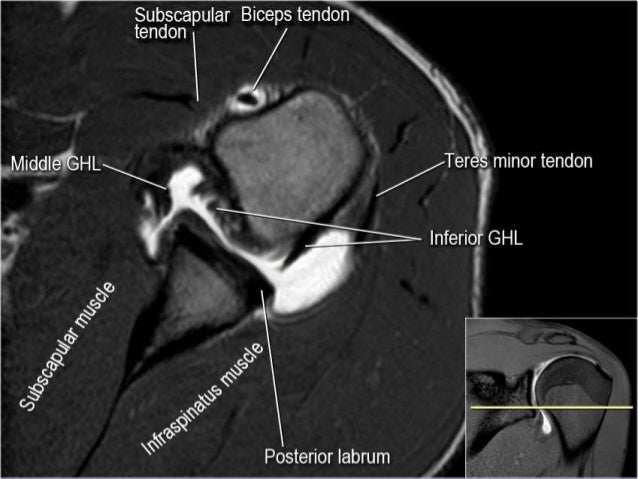

27 axial anatomy 28 the axillary artery begins at the lateral border of the first rib as a continuation of the subclavian artery.

The hagls and bufords and alpsas and mumfords, not to mention the dreaded and expanding categories of slap lesions. T/f the snr of the shoulder is largely… 16 terms. Clinical magnetic resonance imaging, 3rd edition (sample book chapter). Therefore a ct or mri of the shoulder is frequently.